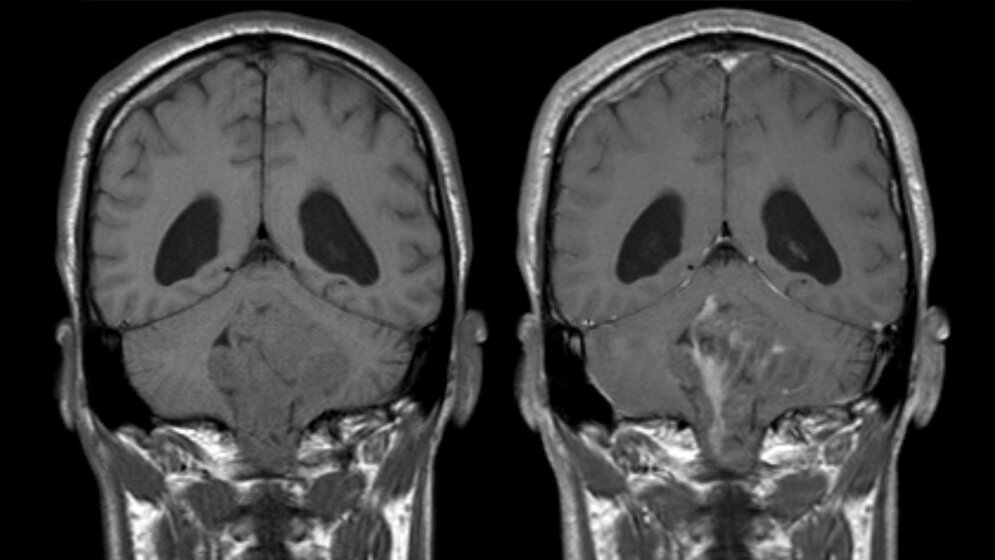

Eine wesentliche Erkenntnis der Forscher/-innen bestehe im Nachweis, dass Ependymomzellen aus einer bestimmten Stammzellnische des Gehirns entstehen. Damit weisen sie auch oft Eigenschaften von Stammzellen auf. Stammzellen besitzen die Fähigkeit, andere Körperzellen zu ersetzen und zu Körperzellen mit verschiedenen Funktionen (z.B. Nervenzellen) heranzureifen (Ausdifferenzierung). Solange sie noch unreif, also undifferenziert sind, können sie sich im Prinzip unbegrenzt vermehren. Sind die Zellen entartet, entsteht eine besonders aggressive Form von Krebs. Johannes Gojo, Facharzt und Forscher an der Universitätsklinik für Kinder- und Jugendheilkunde der MedUni Wien und des Universitätsklinikums AKH Wien sowie am Institut für Krebsforschung der MedUni Wien, Mitglied des CCC sowie des Comprehensive Center for Pediatrics (CCP) der MedUni Wien und des AKH Wien und Erstautor der Studie betont: „Wir haben gesehen, dass die einzelnen Zellen von Ependymomen innerhalb des Tumors verschiedene Entwicklungsstadien durchlaufen. Jene mit aggressivem Verlauf weisen viele unreife Zellen auf, das heißt, sie sind Stammzellen sehr ähnlich. Tumoren, bei denen sich ein Großteil der Zellen in einem ausgereifteren Zustand befand, zeigten eine günstigere Prognose. Dieses Ergebnis könnte uns einen Ansatzpunkt für neue Therapiekonzepte liefern.“ Es erklärt außerdem, warum sich Ependymome bei Kindern häufig aggressiver verhalten als bei Erwachsenen: Bei ihnen ist der Anteil an undifferenzierten, stammzellartigen Ependymomzellen höher als bei Erwachsenen.